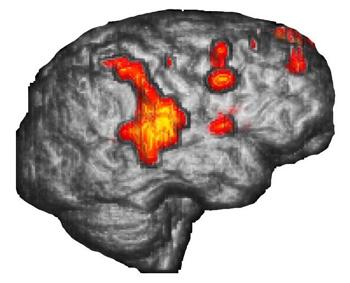

La representación de superficie es un método de postprocesamiento en computadora que retira la piel y el cráneo, y nos permite ver la superficie del cerebro. Se muestra la anatomía de las circunvoluciones y los surcos de la misma manera que el neurocirujano ve el cerebro. Pueden superponerse mapas funcionales sobre estas imágenes. Es posible que se produzca cierta activación en la parte profunda de los surcos, la cual puede presentarse en estas imágenes filtrándose a través de la superficie cortical.

Hemisferio derecho en una representación de superficie tridimensional

Joven diestro de 15 años de edad con epilepsia intratable que realiza una tarea de "repetición verbal". La representación de superficie muestra magníficamente la activación que ocurre en el tercio posterior de la circunvolución temporal superior derecha que se extiende hacia la circunvolución supramarginal y el área 7 de Brodmann. Las áreas de activación se muestran mejor que con las imágenes de resonancia magnética bidimensional convencional.